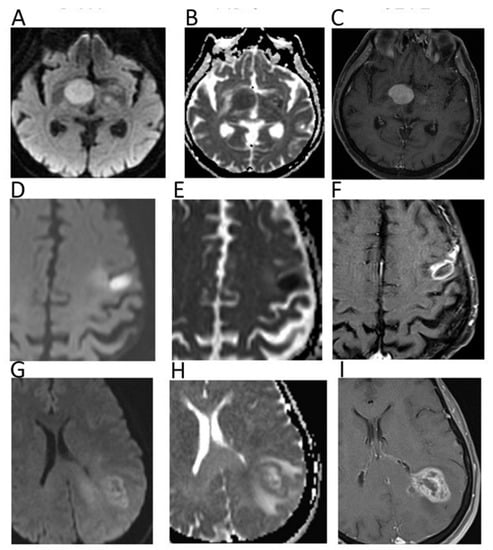

2. Neuro

| Neuroradiology | Yamasaki, F.; et al. Radiology. 2005 [3] | Retrospective; 275 patients with brain tumors; 1.5T MRI. | Mean ADC values are useful for differentiating brain tumors such DNT (2.546 × 10−3 mm2/s) and malignant lymphomas (0.725 × 10−3 mm2/s) versus glioblastomas (1.079 × 10−3 mm2/s) and metastatic tumors (1.149 × 10−3 mm2/s), and ependymomas (1.230 × 10−3 mm2/s) versus PNETs (1.079 × 10−3 mm2/s). |